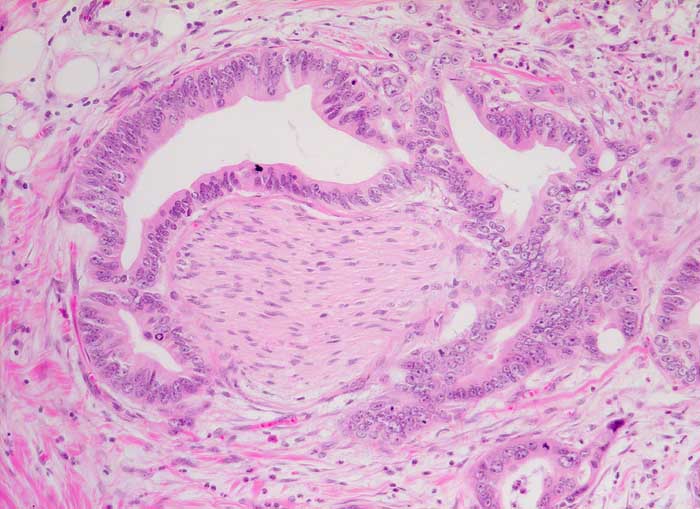

PathoPic – image database / PathoPic ID 5884 - duktales Adenokarzinom des Pankreas: Nervenscheideninvasion

duktales Adenokarzinom des Pankreas: Nervenscheideninvasion

Drüsen mit deutlich atypischer Epithelauskleidung umschliessen konzentrisch einen peripheren Nerven.

Der Nachweis einer zirkulären Infiltration der Nervenscheiden durch atypische Drüsen bestätigt die Malignität des Tumors und ist vor allem unter Schnellschnittbedingungen ein hilfreiches Merkmal.